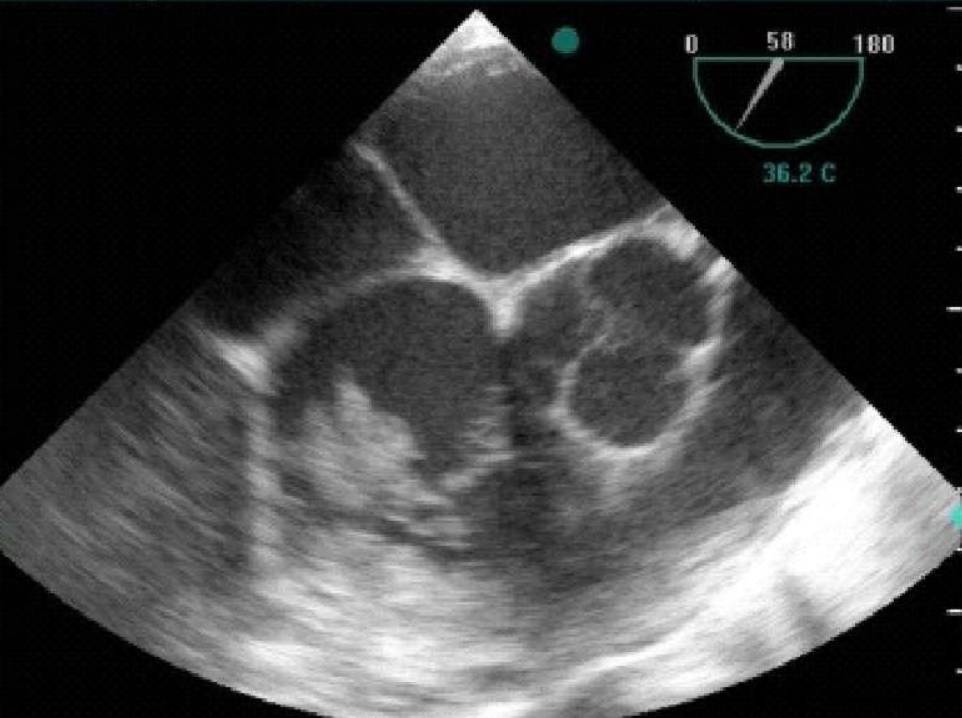

The patient subsequently underwent heart echocardiography (both transthoracic and transoesophageal) where vegetations were found in the tricuspid valve (Fig. 1). Otherwise, the heart function was normal.

Regarding endocarditis, heart ultrasonography is the primary imaging modality, as it visualises vegetations inside the heart and establishes the diagnosis [4].